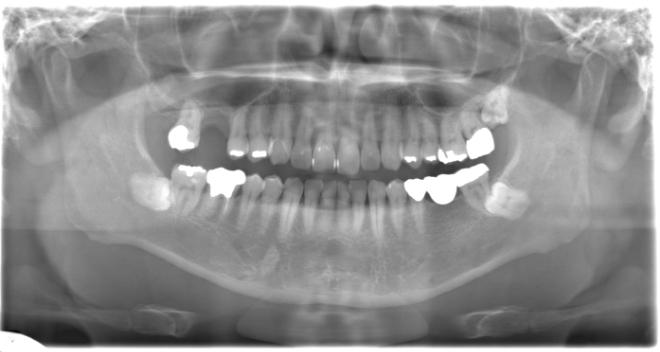

インプラント、ソケットリフト、ダイレクトボンディング、ジルジニアクラウン

| 治療期間 | 1年6ヶ月 |

| 治療費 | インプラント1本500,000円 ソケットリフト110,000円 ダイレクトボンディング〜ジルジニアクラウン1本30,000円〜170,000円 |

| 年齢・性別 | 40代男性 |

| 備考 | 右上の欠損部へのインプラントを希望で来院されました。 左下のブリッジの下にものが挟まりやすいとのことでブリッジ部分もインプラント埋入を希望されました。口腔内の銀歯も全て綺麗にやりかえたいとのことで、ダイレクトボンディングやセラミックインレーやジルコニアクラウンでやりかえていきました。 右上6番のインプラント埋入時にはソケットリフトで骨造成を行なっています。 見た目だけではなく噛みやすくなりとても満足されています。現在はエアフローのクリーニングやホワイトニングで通院されています。 |